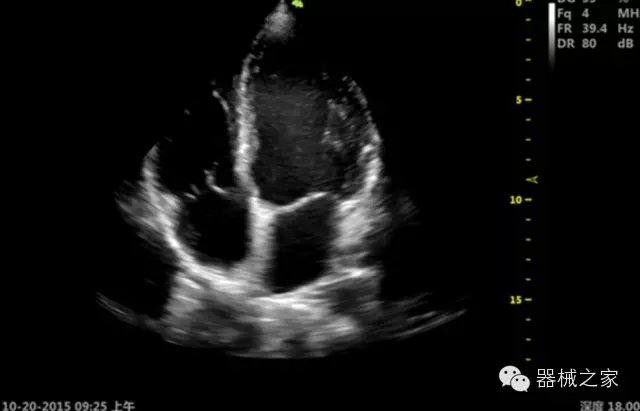

臨床圖片賞析

·飛依諾特有心臟純凈波探頭提供更好的穿透力和彩色敏感度,以及結(jié)合TView梯形拓展改善困難病人深部組織成像;

·獨(dú)有RF敏感血流使得心臟血流完美呈現(xiàn);